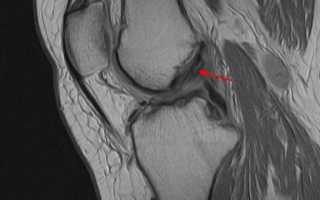

МРТ коленного сустава показывает повреждение (отек, разволокнение, частичный разрыв) передней крестообразной связки.

image